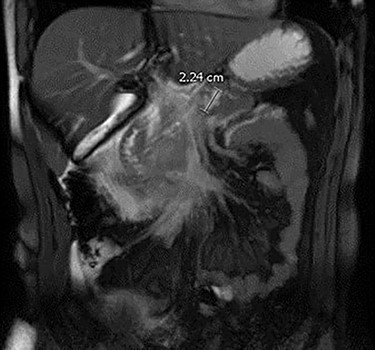

The patient is a 21-year-old male who presented for surgical consultation after his second hospitalization for acute pancreatitis over a 6 month period. During his most recent admission, magnetic resonant imaging (MRI) demonstrated a 2.2 cm cyst in the pancreatic body with dilatation of the main pancreatic duct to 5 mm suggestive of a mixed duct IPMN (Fig. 1). Presence of two ‘worrisome’ features, which included lesion size >2 cm and main duct dilation >5 mm according to the Fukuoka 2017 management guidelines, prompted a referral for endoscopic ultrasound (EUS) and cyst aspiration with pathologic fluid analysis [7]. A laboratory workup was performed, to include carbohydrate antigen 19-9, carcinoembryonic antigen and pancreatic islet antibody.